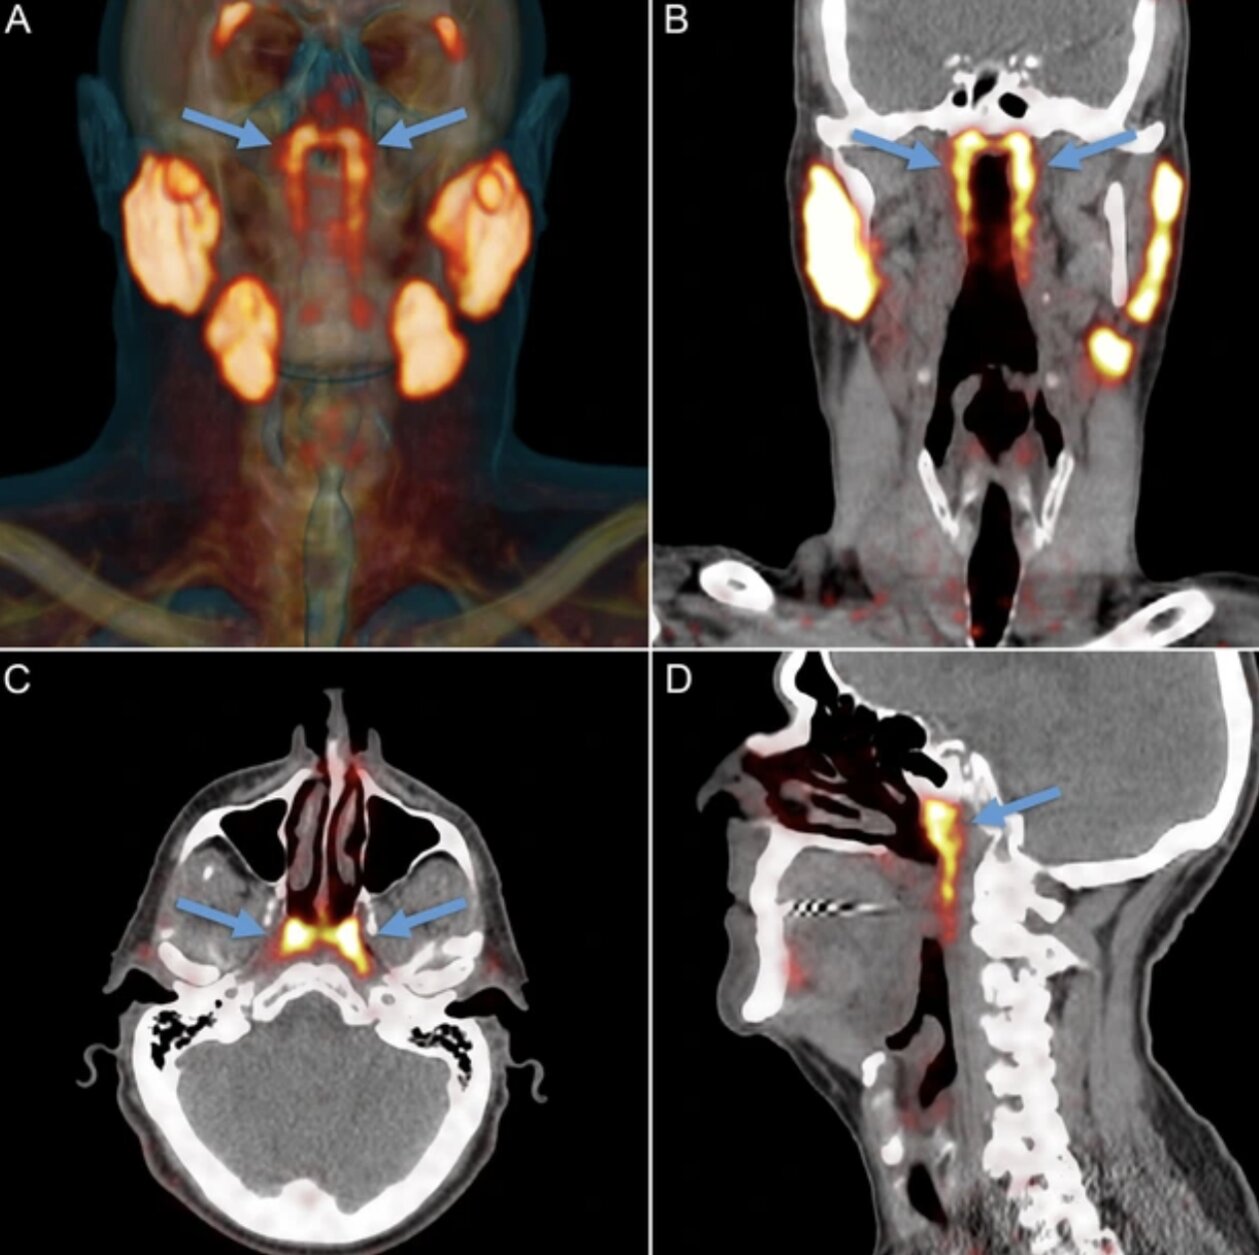

Theo PubMed, vào năm 2020, các nhà nghiên cứu Hà Lan công bố phát hiện một cặp tuyến nước bọt mới nằm ngay phía sau mũi, trong khu vực nối giữa khoang mũi và họng. Sau đó, nó đã được các chuyên gia đặt tên là tuyến nước bọt ống hầu (tubarial salivary glands). Phát hiện này lập tức làm dậy sóng truyền thông và cộng đồng khoa học vì nếu đúng, nó sẽ bổ sung vào "bản đồ" giải phẫu người vốn tự hào có 3 cặp tuyến nước bọt lớn đã được biết đến lâu nay.

Theo NKI, câu chuyện bắt đầu không phải từ phòng mổ giải phẫu mà từ… máy PET/CT cho bệnh nhân ung thư tiền liệt tuyến. Khi các bác sĩ tiêm chất đánh dấu và soi hình ảnh, họ thấy hai vùng sáng bất thường ở vòm họng xuất hiện nhất quán trong hàng loạt bệnh nhân đã gợi ý có một cấu trúc tuyến lớn hơn những "tuyến nhỏ rải rác" mà sách y đã mô tả trước đó. Khám nghiệm thêm trên xác và phân tích mô cho thấy tồn tại mô tuyến với nhiều ống dẫn, đủ để các tác giả đặt vấn đề đây là một "vùng tuyến" có thể coi là cơ quan.